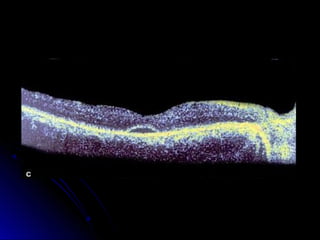

 The  vitreous is the black space on the top

of the image

 We can identify the fovea by the normal

depression

 The nerve fiber layer (NFL) and the retinal

pigment epithelium (RPE) are easily

identifiable layers as they are more highly

reflective than the other layers of the

retina

 This higher reflectivity is represented by

the "hotter" colors (red, yellow, orange,

white) in the false color representation of

the OCT 3.

 The middle layers of the retina, between

the NFL and RPE, are much less easily

identifiable in the scan.